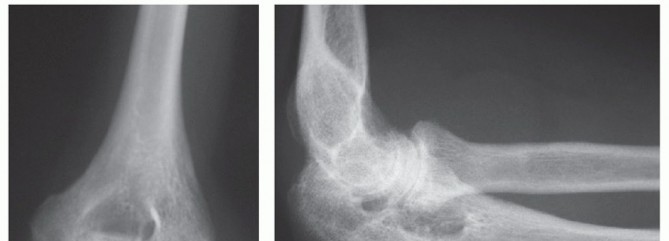

PATIENT HISTORY AND PHYSICAL FINDINGS Distal humerus fractures occur in two age groups: Younger patients who …

DEFINITION Fractures involving the proximal region of the humerus that provide the supporting framework for t…